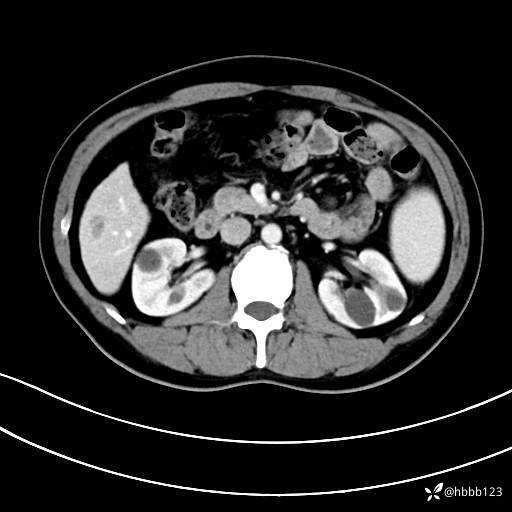

门诊完善上腹部CT平扫+增强。

静脉期: